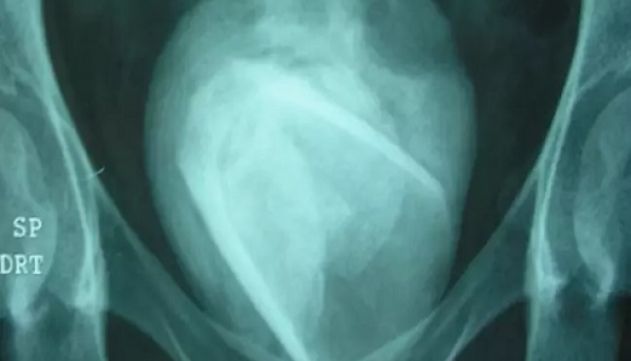

Raio-x mostrou um copo envolto por uma pedra de 8 cm de largura na bexiga

Segundo o The Sun, o raio-x mostrou um copo envolto por uma pedra de 8 cm de largura na bexiga dela. Com isso, a mulher revelou que havia usado o objeto como brinquedo sexual quatro anos atrás. Ela havia inserido o item na uretra – onde a urina passa –, em vez da vagina.

Os profissionais da saúde fizeram uma cirurgia para remover o item e, quando abriram a pedra de 8 cm que estava na bexiga, encontraram o copo ainda intacto. As pedras, que geralmente são pequenas, "se desenvolvem a partir de massas duras de minerais quando a urina não é evacuada adequadamente". Mas também podem crescer em torno de objetos estranhos alojados na bexiga, como o copo de vidro.